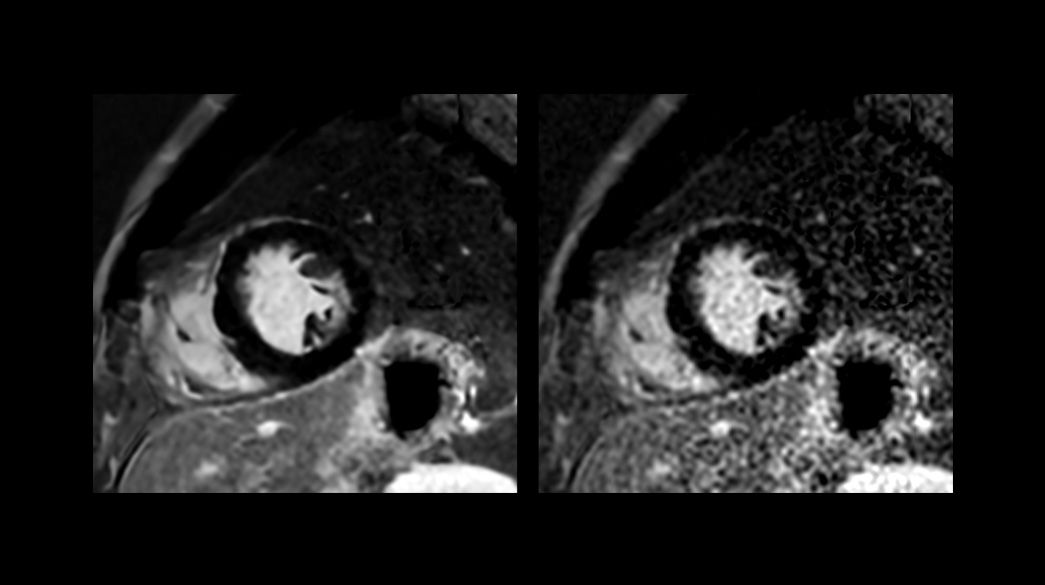

CardioMaps – compatible with AIR™ Recon DL

T1 Mapping as a choice is based on an GE HealthCare exclusive sequence SMART1Map or on an inversion recovery sequence MOLLI

StarMap – compatible with AIR™ Recon DL

A non-invasive technique that evaluates iron overload in the myocardium and liver